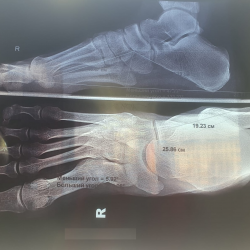

Здравствуйте, по результату рентгеннограммы полая стопа, результат прикладываю. По осмотру и описанию ортопеда полая стопа, при чем с молоточкообразными 2 и 3 пальцами, плантарный фасциит,...